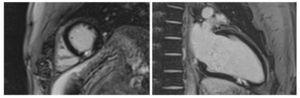

Before the discovery of ventricular premature beats in the stress test is requested signal-averaged ECG: normal. Cardiac Holter: sinus rhythm. HR average: 66 bpm, 2 PVCs in 24 hours. Coronary tomography: epicardial arteries without coronary lesions and cardiac magnetic resonance with adenosine: absence of inducible ischemia, LVEF 60%, focal area of transmural late gadolinium enhancement in the inferior segment of the left ventricle (Fig. 3).

Figure 3. Cardiac resonance, transmural late enhancement.